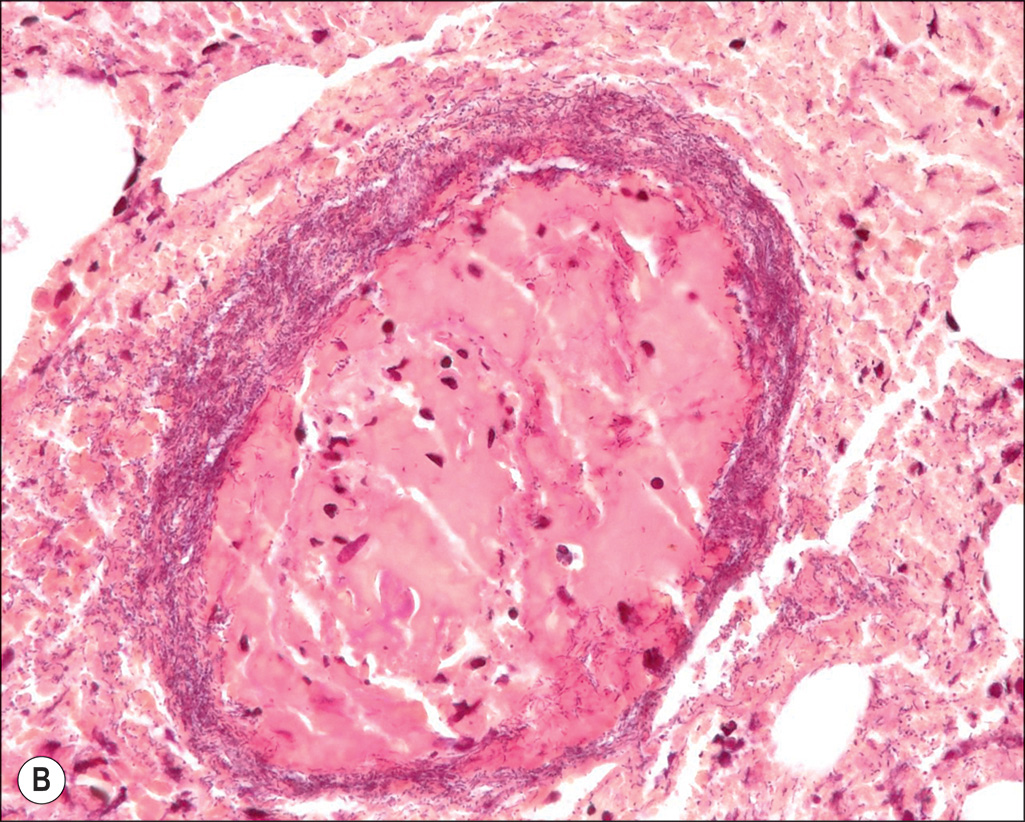

Ecthyma gangrenosa. A tissue-invasive burn wound infection here seen in a 7-year-old girl transferred to our hospital after a 6-week treatment at another hospital. (A) Note the extensive greenish and slime-coated wound consistent with an invasive wound infection. The patient died subsequently from an overwhelming hematogenously spread pneumonia. (B) The vessel wall at 40× magnification micrograph shows a clear bacterial infiltration. (C) A typical purplish ecthyma gangrenosa lesion in a 35-year-old man.

(C, From Omar P. Sangüeza, MD; Professor and Director of Dermatopathology, Wake Forest University School of Medicine, North Carolina.)